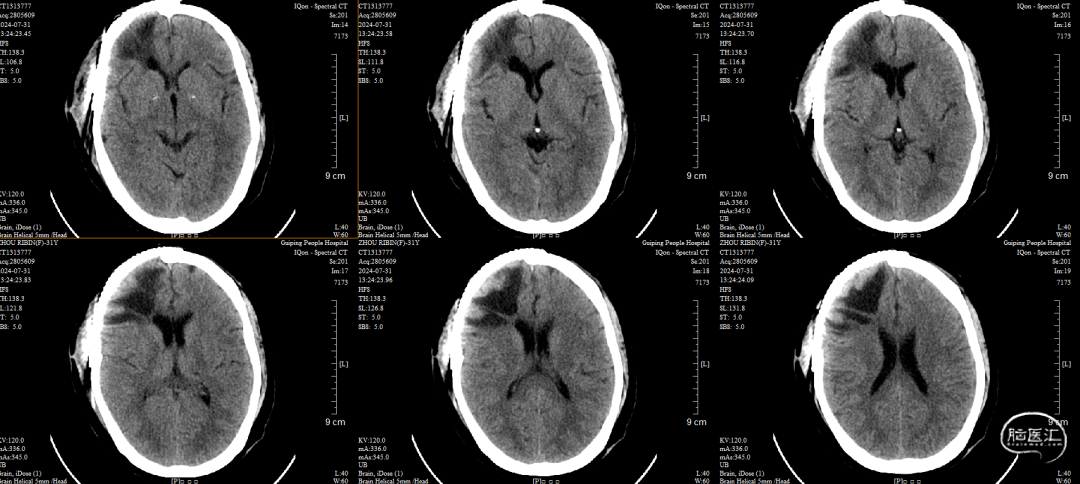

术后CT